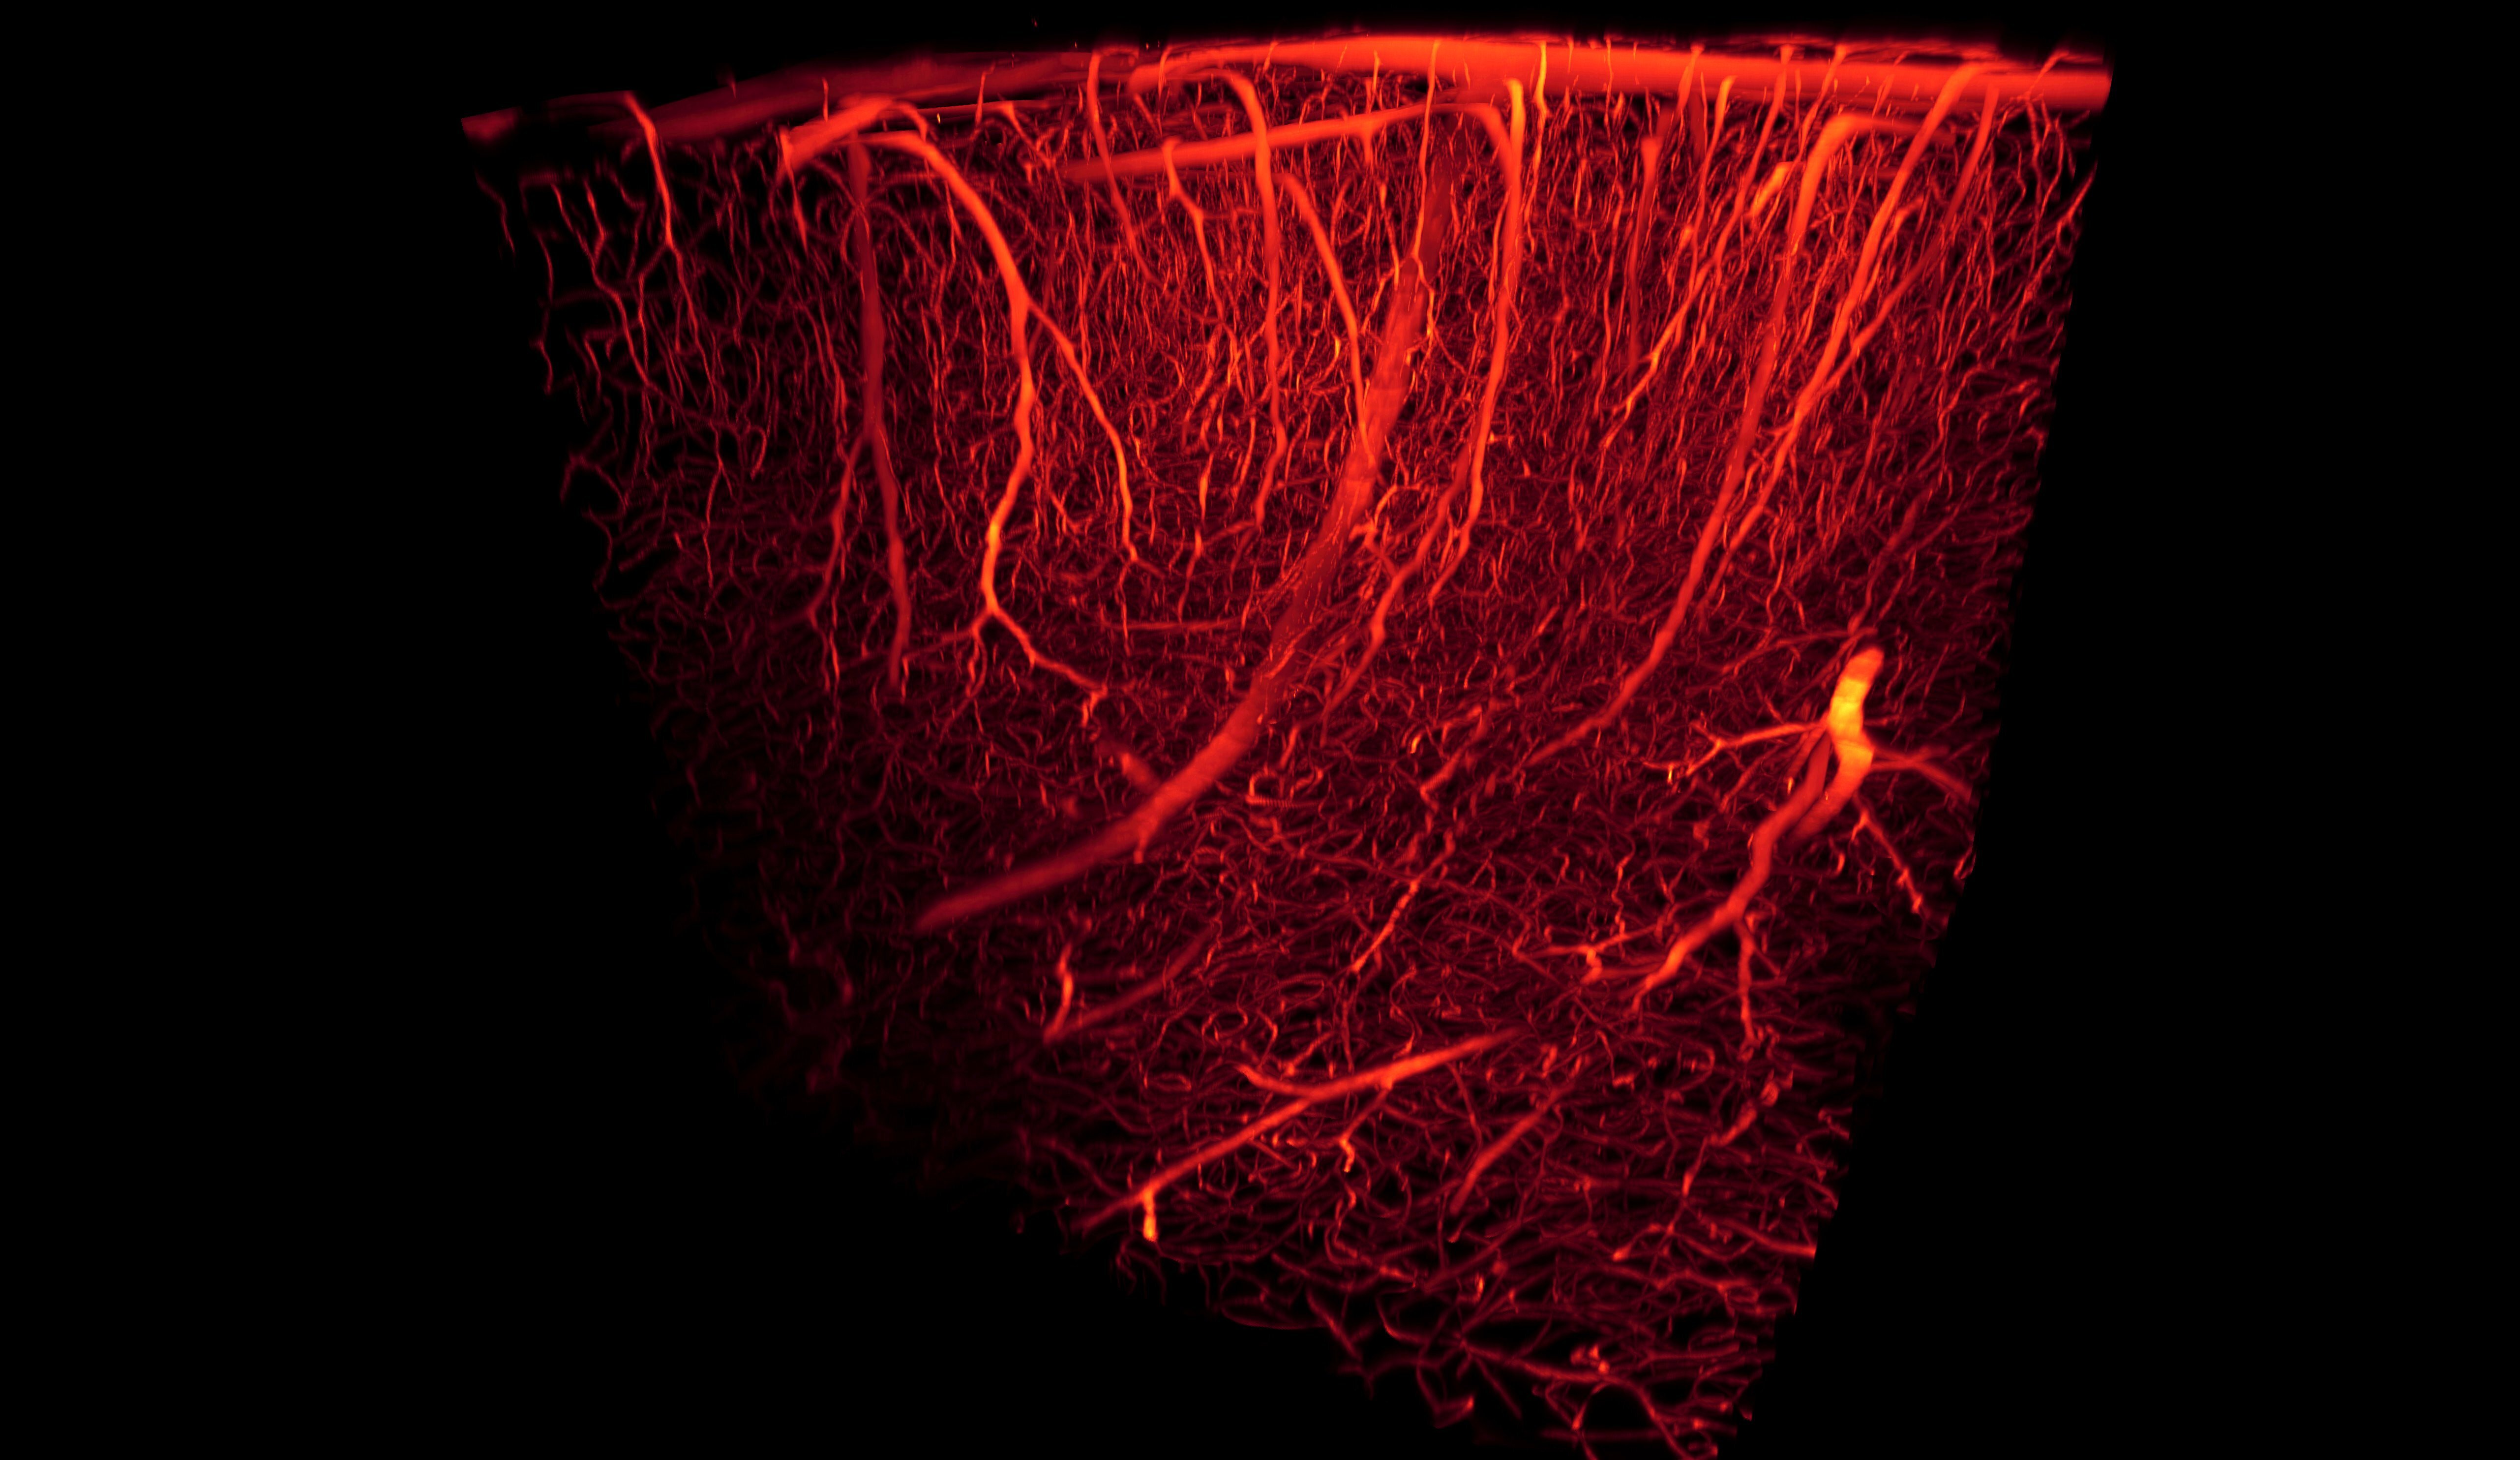

Нарушение мозгового кровообращения приводит к слабости и онемению одной половины тела. Это может быть рука, нога, лицо: человеку сложно симметрично улыбнуться. Также нарушается качество зрения, начинает двоиться в глазах, появляется сильная головная боль.

Фото: commons.wikimedia.org, Antonino Paolo Di Giovanna, Creative Commons Attribution-Share Alike 4.0 International license.